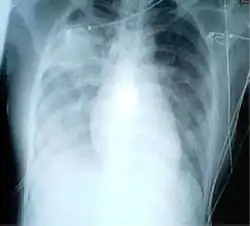

Pleural abnormalities

Fluid in space between the lung and the chest wall is termed a pleural effusion. There needs to be at least 75 mL of pleural fluid in order to blunt the costophrenic angle on the lateral chest radiograph and 200 mL of pleural fluid in order to blunt the costophrenic angle on the posteroanterior chest radiograph. On a lateral decubitus, amounts as small as 50ml of fluid are possible. Pleural effusions typically have a meniscus visible on an erect chest radiograph, but loculated effusions (as occur with an empyema) may have a lenticular shape (the fluid making an obtuse angle with the chest wall).

Pleural thickening may cause blunting of the costophrenic angle, but is distinguished from pleural fluid by the fact that it occurs as a linear shadow ascending vertically and clinging to the ribs.